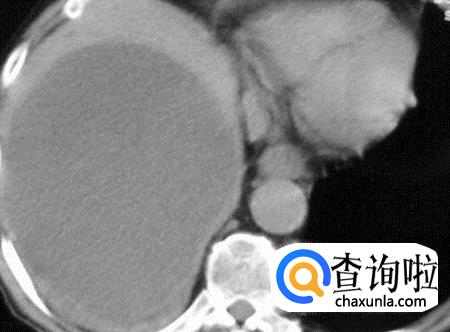

首先我想要告诉大家的是如果你有肝囊肿的话,如果没用什么病症的话,不要去管它,因为肝囊肿对人体并没有什么危害。

有的人身体中的肝囊肿肿块很大,就非常的着急,想要手术切除,在这里我要说的是,没关系的,有的还像是拳头这么大

但是有的太大了的确影响到了人的呼吸运动,可以到医院采取切割引流的方式解决这个问题。